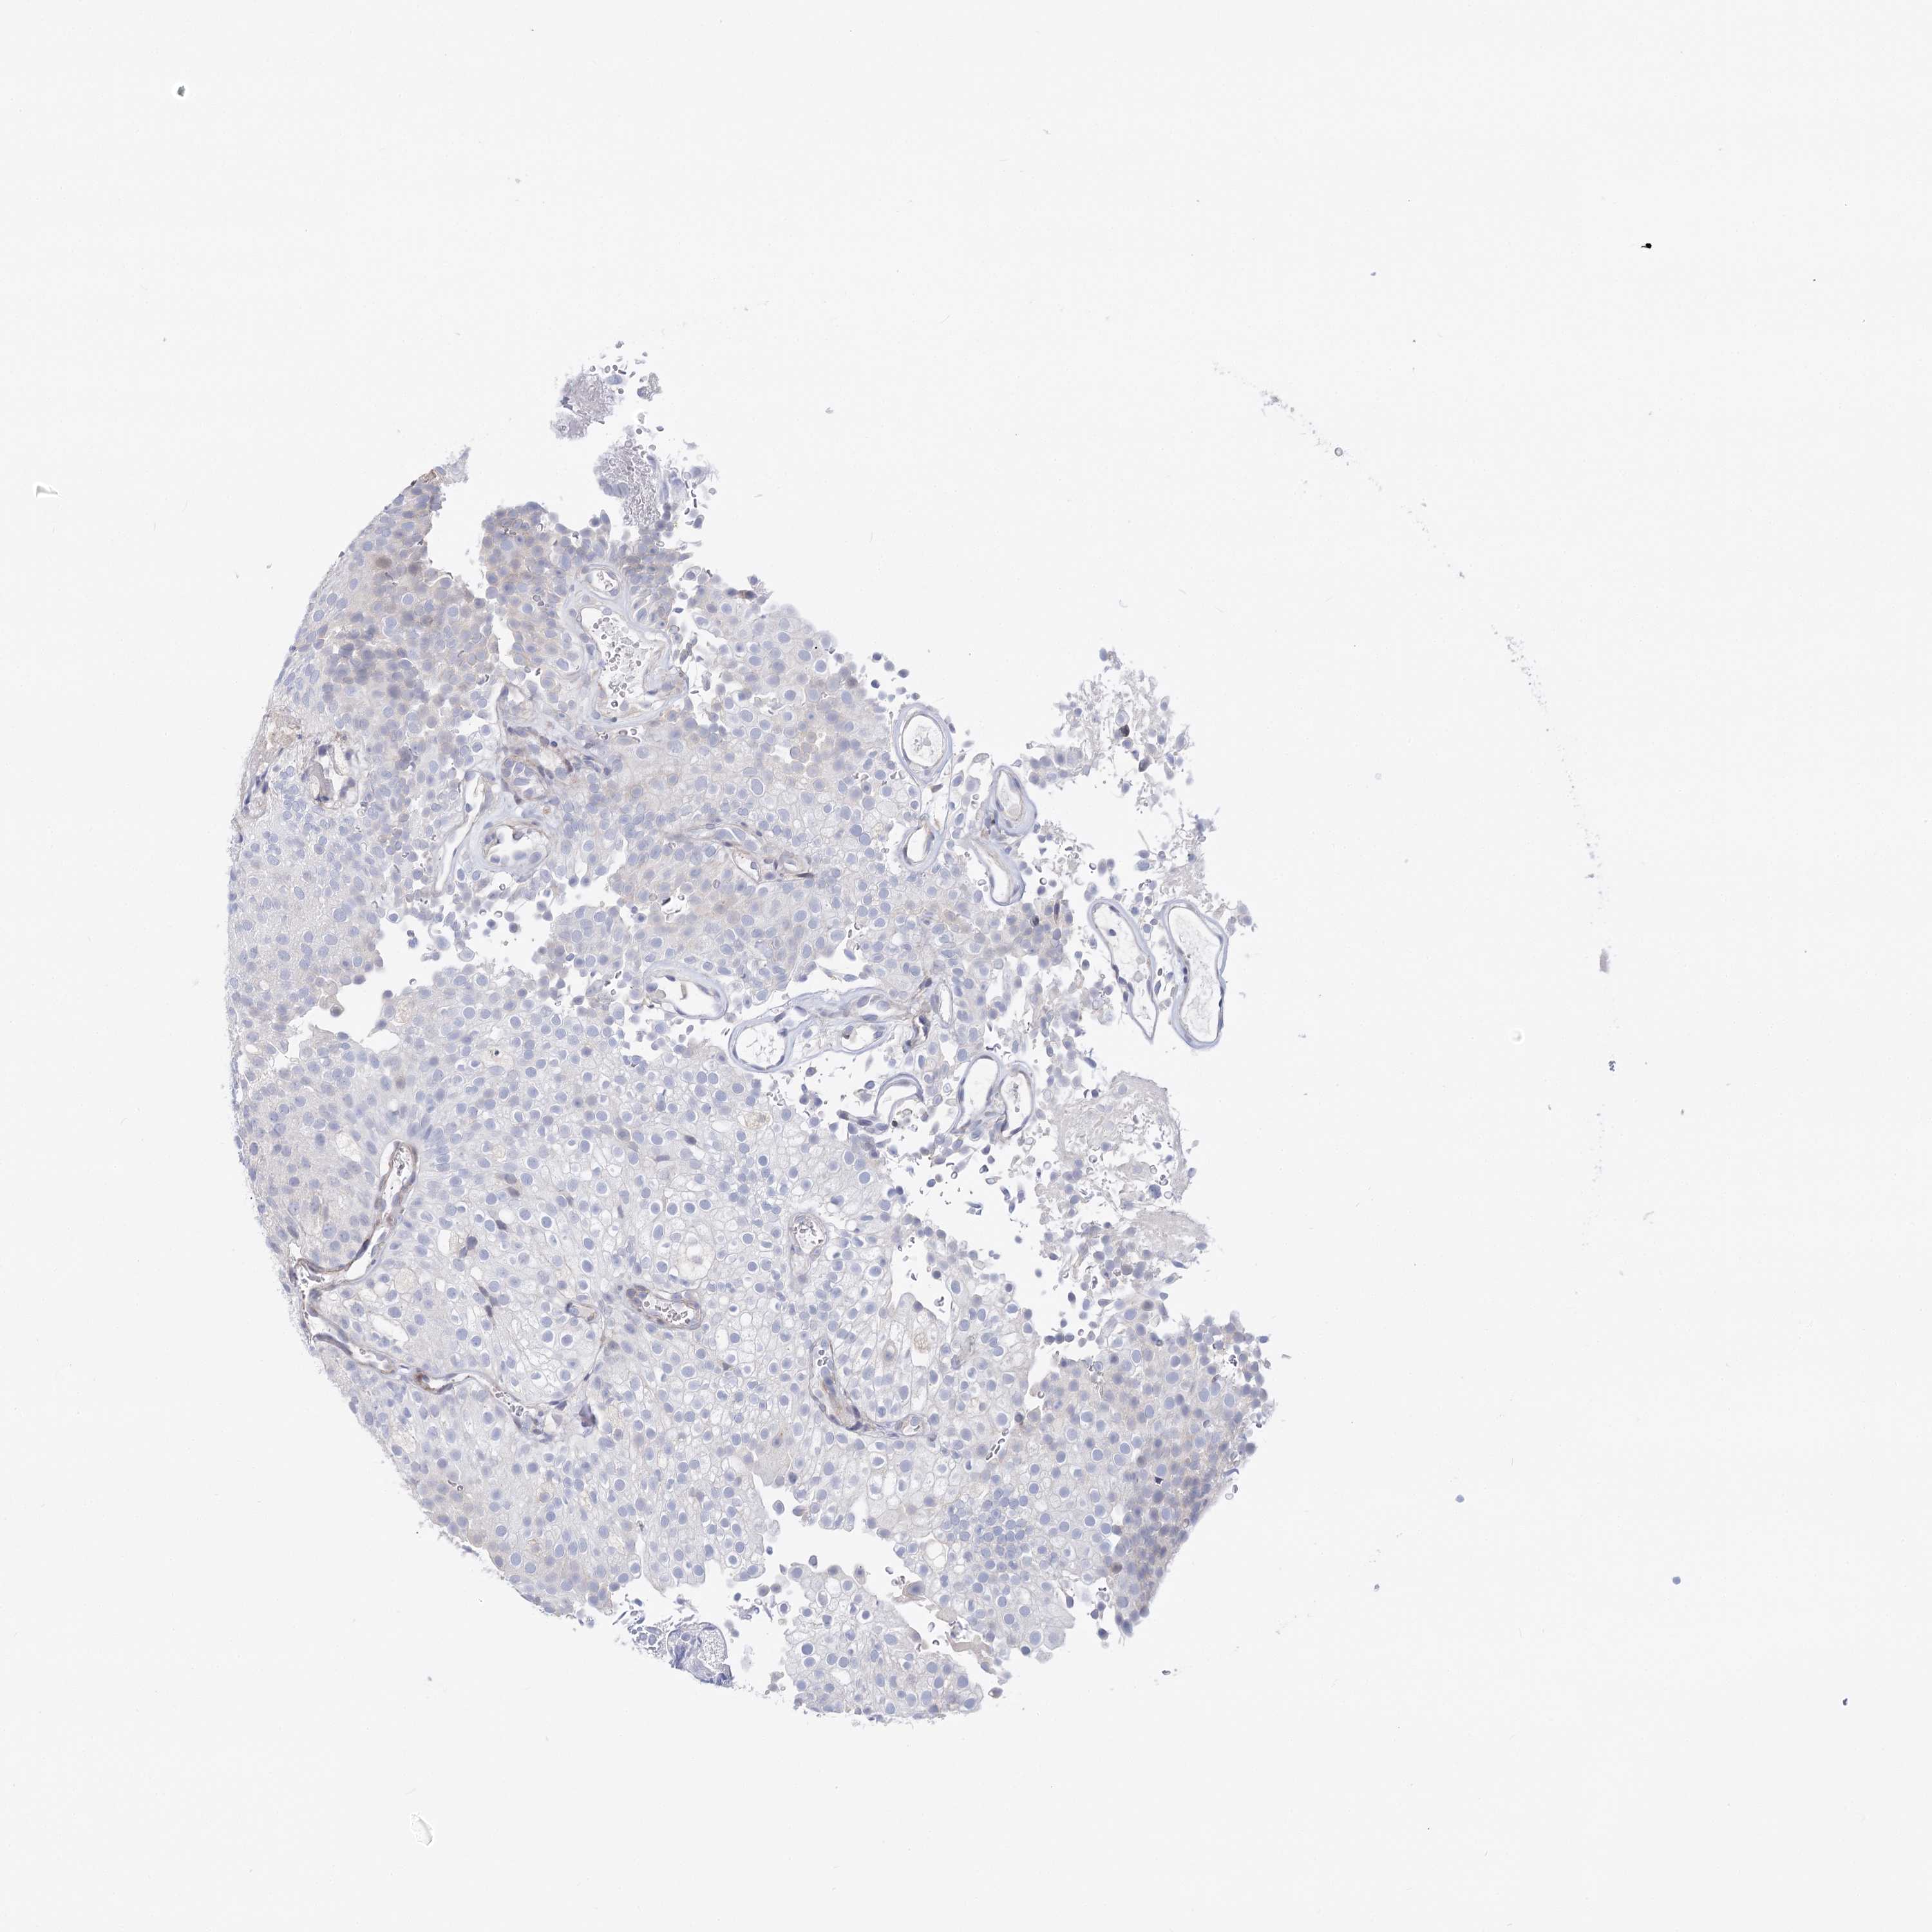

UROTHELIAL CANCER - Protein expressioni

A mouse-over function shows sample information and annotation data. Click on an image to view it in a full screen mode. Samples can be filtered based on level of antibody staining by selecting one or several of the following categories: high, medium, low and not detected. The assay and annotation is described here.

Note that samples used for immunohistochemistry by the Human Protein Atlas do not correspond to samples in the TCGA dataset.

Antibody stainingi

Antibody staining in the annotated cell types in the current human tissue is reported as not detected, low, medium, or high, based on conventional immunohistochemistry profiling in selected tissues. This score is based on the combination of the staining intensity and fraction of stained cells.

Each image is clickable and will lead to virtual microscopy that enables deeper exploration of all samples and also displays staining intensity scores, fraction scores and subcellular localization as well as patient and tissue information for each sample.

Antibody HPA038289

Antibody HPA038290

Staining

High

Medium

Low

Not detected

Intensity

Strong

Moderate

Weak

Negative

Quantity

>75%

75%-25%

<25%

None

Location

Nuclear

Cytoplasmic/membranous

Cytoplasmic/membranous,nuclear

Urothelial carcinoma, Low grade